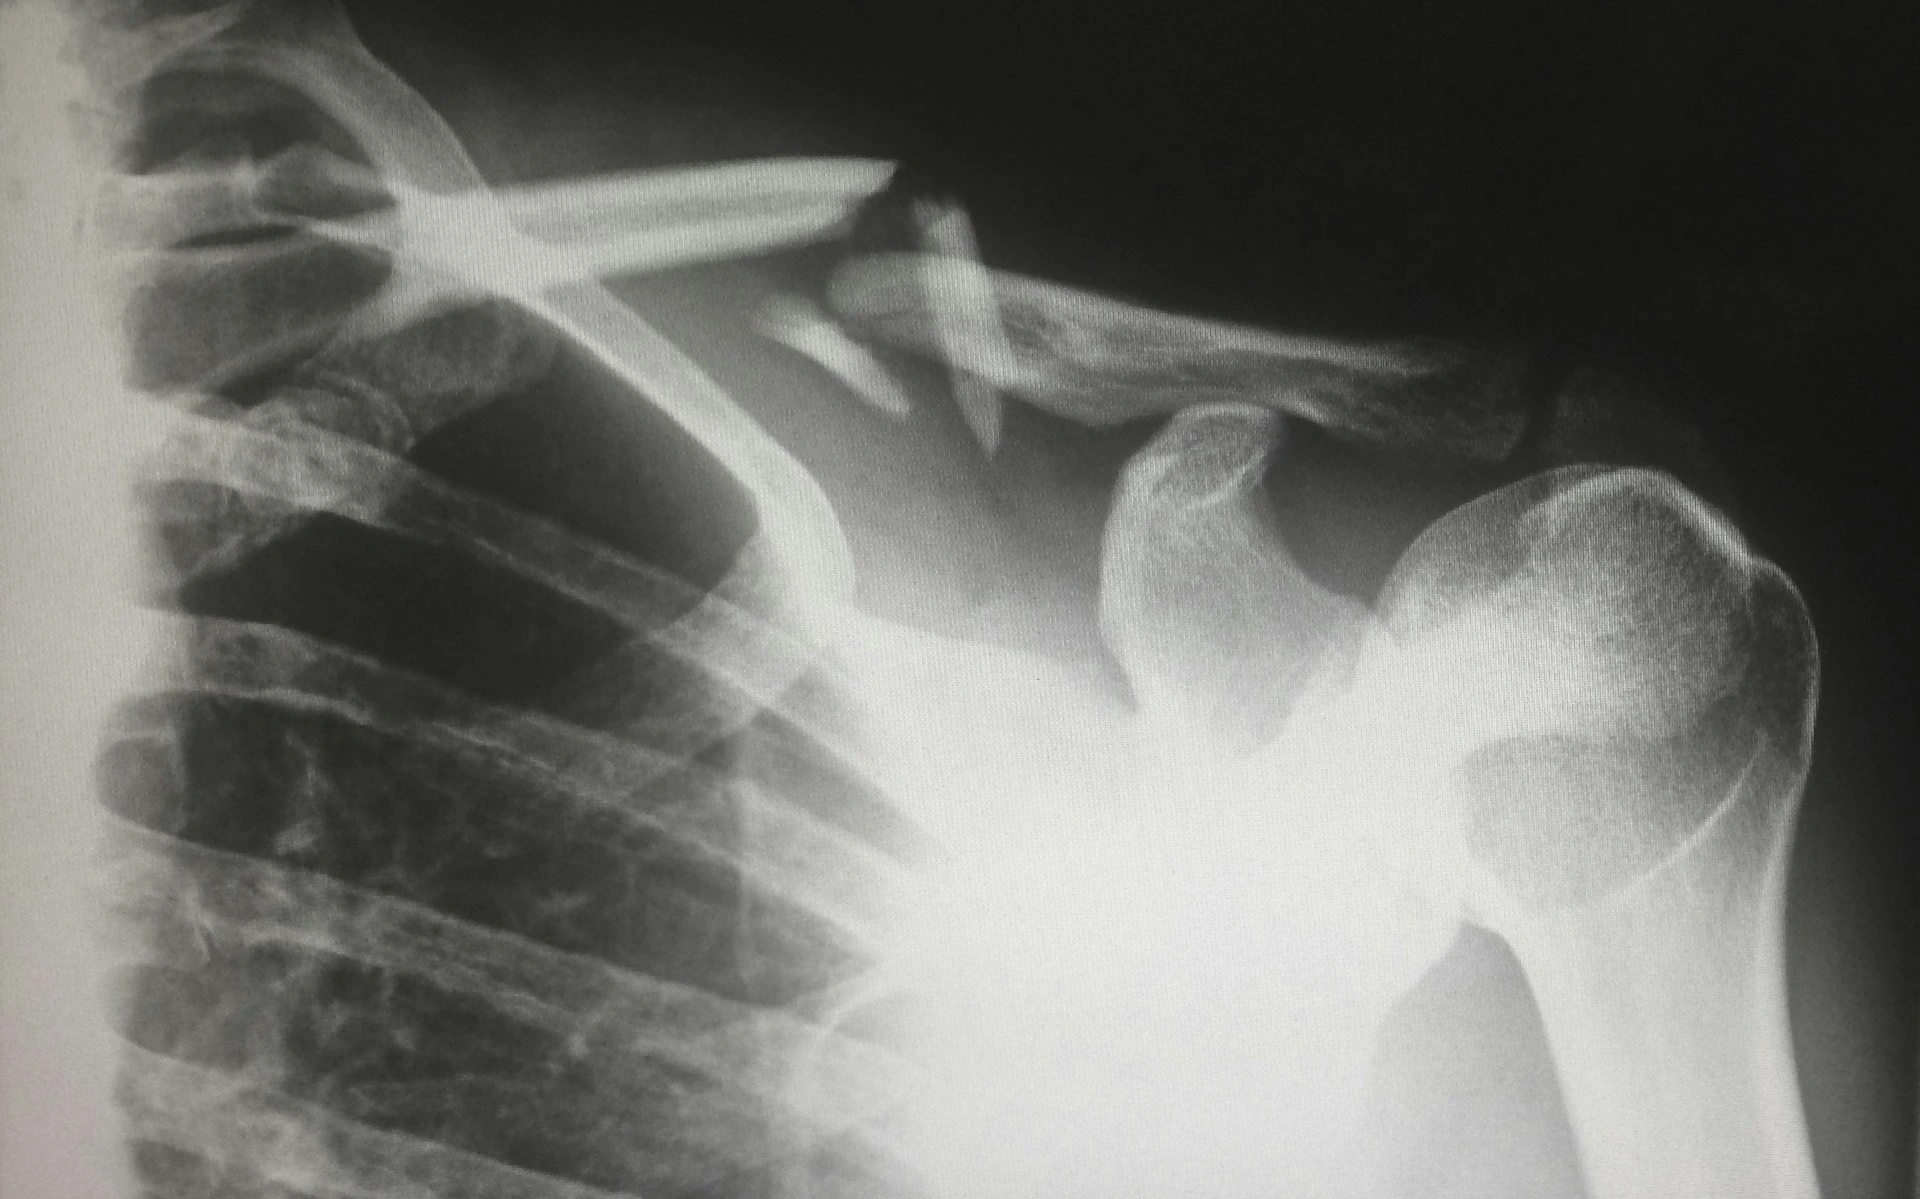

К сожалению, кости сами по себе не болят, и именно поэтому остеопороз называют «тихой болезнью». Карина Ким рассказала о косвенных признаках, на которые стоит обратить внимание:

- Частые переломы даже при небольших травмах. Условно: человек споткнулся, упал с небольшой высоты — и уже трещина или перелом.

- Снижение роста — если вы замечаете, что «усаживаетесь» или становитесь ниже на 1–2 сантиметра, это может быть признаком уменьшения плотности костей позвоночника.

- С помощью денситометрии — это специальное исследование, которое визуализирует плотность костей.